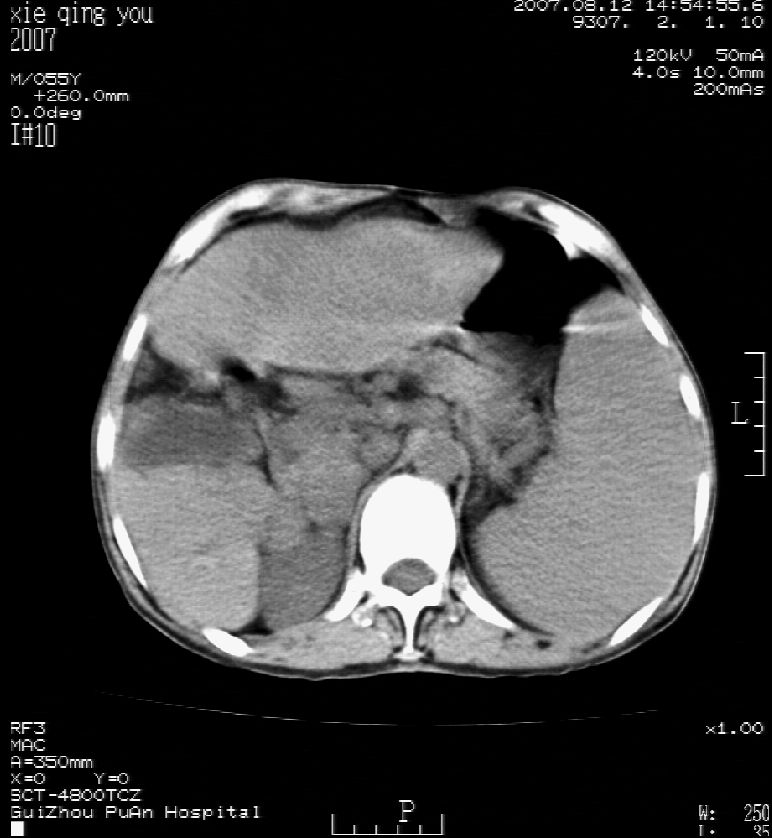

2007年8月片

这个病灶很有意思,怎么可能没有了呢?我考虑当时很可能是肝脏脓肿(b超示囊肿是有可能误诊的,因为影像表现都是低回声吗?),现在脓肿吸收了,肝脏萎缩,肝裂增宽了.别的肝叶代偿增大,不过现在左内叶的确有个占位,肝内多发结石,脾脏比以前大,不排除有肝硬化可能.建议增强扫描给于定性!!!!

肝硬化、脾大、肝内胆管多发结石。肝左叶低密度占位。建议增强扫描.排除肝癌